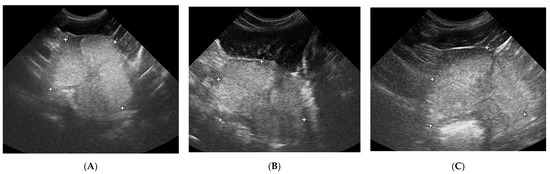

3.1. Prostate B-Mode Appearance